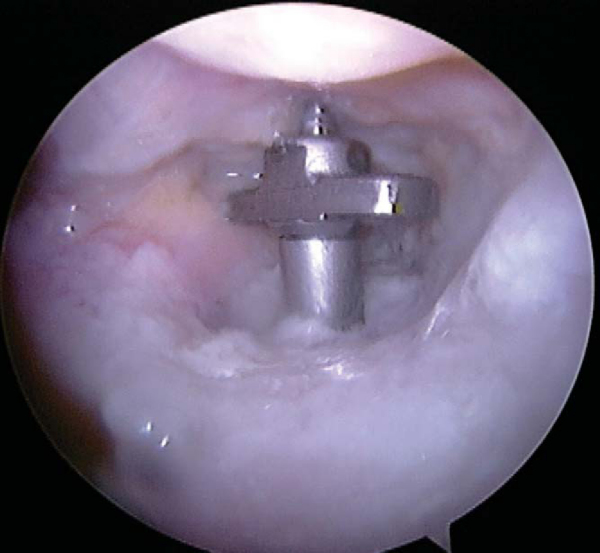

A 3.2-mm transtibial drill hole is placed in the center of the trough corresponding to the 4.5-mm gliding hole in the graft’s tibial bone plug. The transtibial depth is measured, and a 3.2-mm tap is then placed. The graft is more easily passed in an anterior to posterior direction from inside the joint into the trough. The anteromedial parapatellar portal is slightly extended to accommodate the graft’s passage. The sutures are kept separated for each respective graft bundle for later identification and passage. A 4.5-mm fully threaded cortical screw corresponding to the measured length plus 10 mm is used to lag the bone block into the trough (

Fig. 67-10

). We use intraoperative fluoroscopy to verify the location of the graft. The lateral view is easily obtained with the knee in the figure-four position, and the leg is extended for the anteroposterior view.

Figure 67-10 |